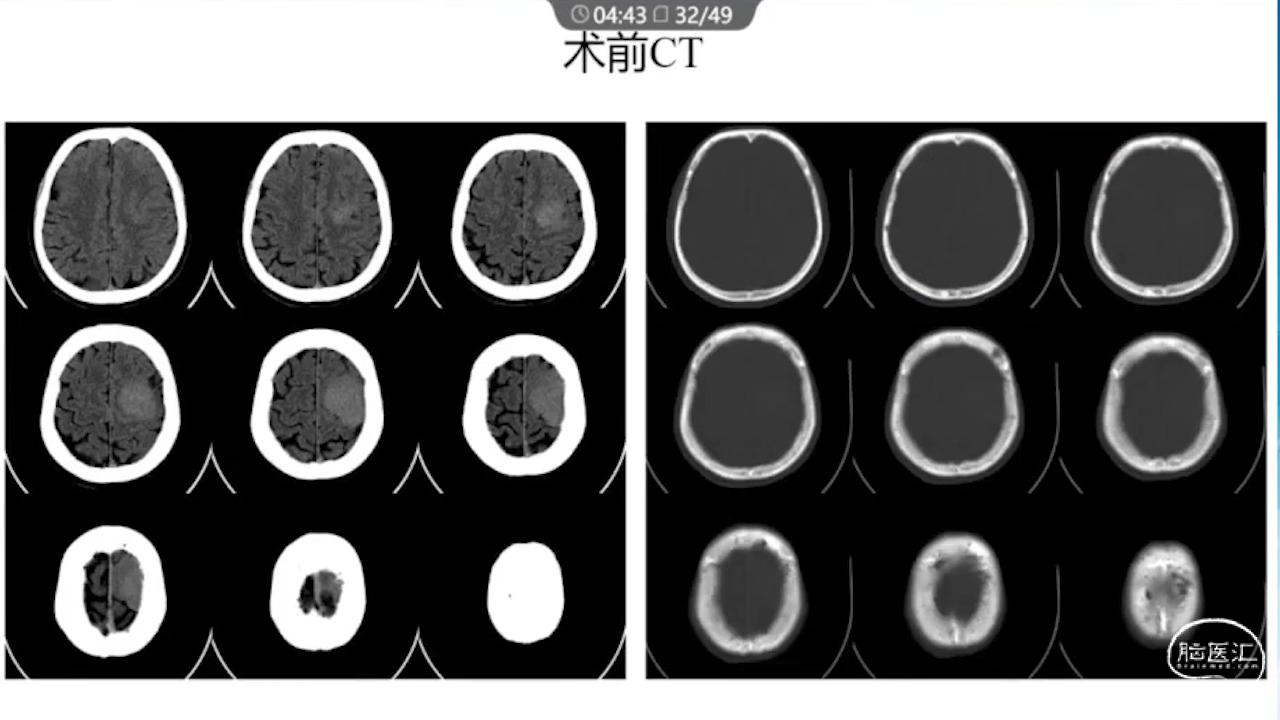

1、术前需要完善的影像学检查、多模态融合及神经导航以进行精确的肿瘤及静脉血管定位。

2、术中硬膜剪开及肿瘤切除时逐步接近功能区,在剪开硬膜前,可行B超定位桥静脉以防误伤,根据桥静脉的位置灵活调整硬膜的剪开方向。